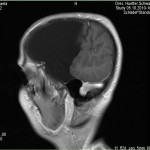

Ich stell euch hier noch eine kleine Galerie rein mit den neuesten Bildern. Ich denke es ist unübersehbar, dass das Ding gewachsen ist, außerdem mir meine komplette Hirnmittelline verschiebt und immer mehr Rücklagerung bekommt und Richtung Hirnsteuerungszentrum drückt. Meine häufiger auftretenden Stürze und Koordinationsprobleme werden also in naher Zukunft sicherlich nicht weniger werden und mein Doc und ich werden uns wohl auch zeitnah über eine weitere Klinik und eine mögliche weitere OP unterhalten müssen.